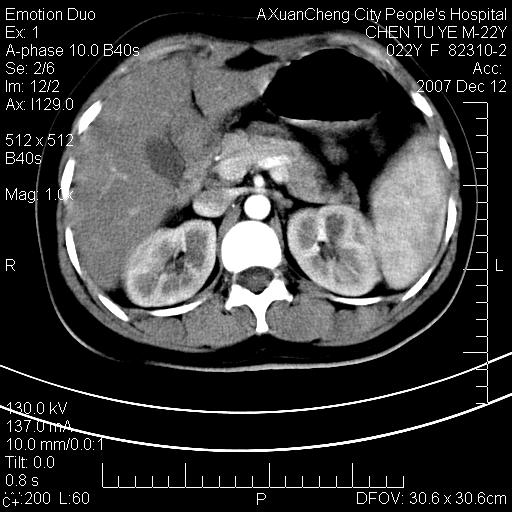

超声提示肝右前叶占位,约2.5cm.

各位战友看看病灶在什么地方,可是右前叶进肝裂部低密度影,平扫ct值约10以下,增强后增高明显

1 脾大,慢性肝损伤. 2 肝脏脂肪侵润.  3 你所指的部位疑点,我没看出有问题.

脂肪肝.楼主所指部位不考虑异常,为肝圆韧带影.

不均匀脂肪浸润,版主所说的病灶为肝园韧带服着点。

考虑肝圆韧带。